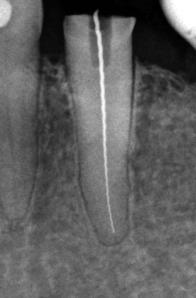

Längenvermessung eines Wurzelkanals